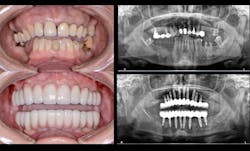

In today’s practice, dental professionals should have imaging that can satisfy all their diagnostic needs. CBCT is an investment that generates a strong return, especially when it covers nearly every routine situation as well as more advanced clinical situations (figure 6). With the systems currently available, you can cost-effectively take the essential first step with 2-D panoramic views and investigate in depth with powerful 3-D imaging. As a result, you can offer and perform more procedures in your practice, improving the overall level of patient care.

Figure 6: A full-mouth implant reconstruction achieved with CBCT